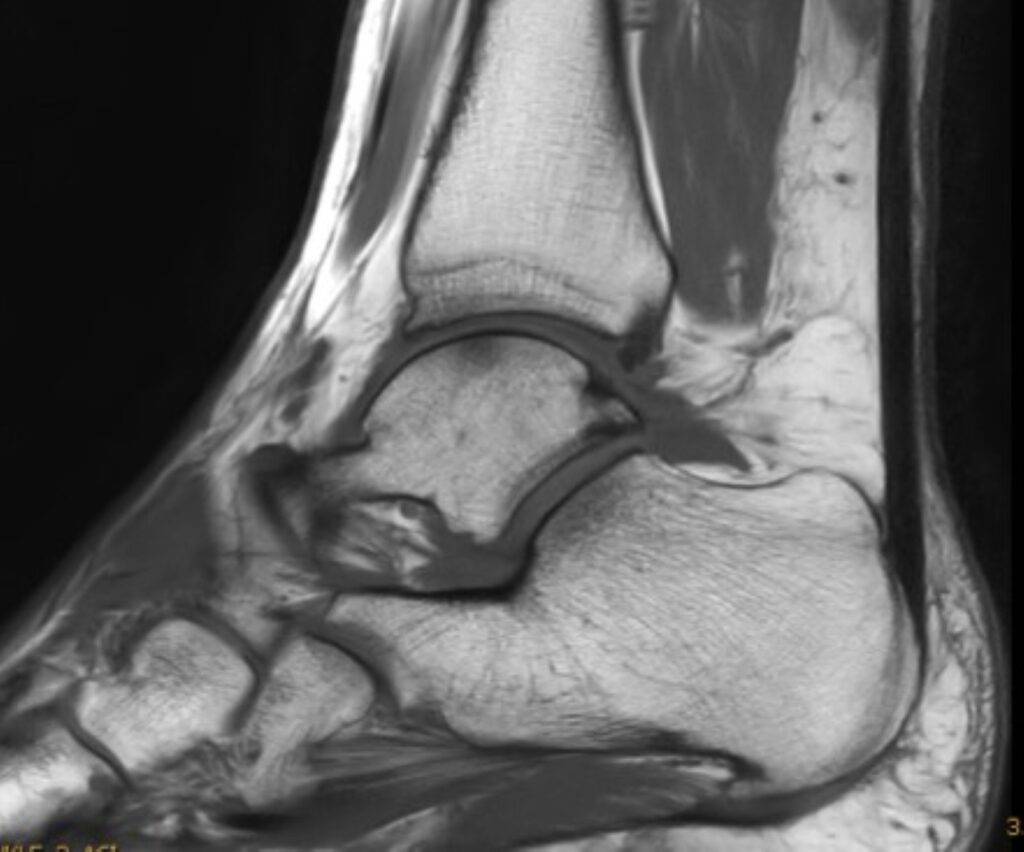

Fuß MRT Bild, verschiedene Perspektiven